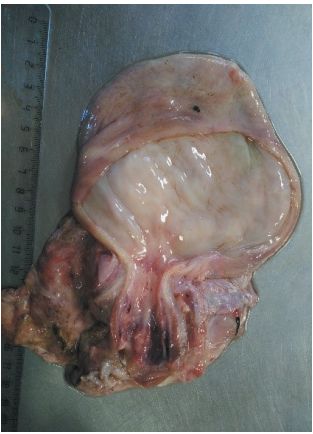

УДК 619:616.995.132 DOI 10.33861/2071-8020-2026-1-46-48 Оригинальное эмпирическое исследование Аксенова П. В. Федеральное государственное бюджетное образовательное учреждение высшего образования «Донской государственный технический университет», Ростовская область, г. Ростов-на-Дону Аннотация. В данной статье впервые описаны патоморфологические изменения при уретральной непроходимости и некрозе пениса у южноафриканского орикса (Oryx gazella). Стриктура и спайки пенильного отдела уретры вследствие склеротизации и некроза вызвали уростаз, приведший к уремии, обструктивной почечной недостаточности, разрывам в шейке мочевого пузыря, дистрофии миокарда, атрофии селезенки, воспалению и некрозу печени, острому отеку легких и ДВС-синдрому. Верхушка пениса вместе с препуцием подверглись сухой гангрене. Выше демаркационной линии отмечены нарушение структурности пещеристого тела пениса, повышенное наличие соединительнотканных компонентов, склероз сосудов и очаговая воспалительная реакция в виде выброса лимфоидных клеток. Мочеполовой канал сужен, местами сращён, имелись свищи. В тканях предстательной железы имелись изменения, характерные для простатита. Ключевые слова: орикс, аутопсия, уремия, уретральная непроходимость, уростаз, обструктивная почечная недостаточность, некроз пениса, пенитальная уретра, шейка мочевого пузыря, токсическая дистрофия, стриктура уретры, уролит, свищ, мочеточники, почки. Ориксы – это вид саблерогих антилоп, обитающих в саваннах и полупустынях Южной Африки. Вид в Красном Листе Международного союза охраны природы и природных ресурсов отнесен к категории «Least concern» (вызывающие наименьшее опасения). Ориксы достаточно успешно разводятся в зоопарках. Однако в ветеринарном аспекте эти животные изучены недостаточно. В частности, не найдено ни одной научной публикации о заболеваниях репродуктивных органов у ориксов. Ветеринарная наука, в целом, не располагает достаточным количеством исследований половой системы у диких копытных, хотя данная сфера у сельскохозяйственных животных охвачена достаточно широко. Так, относительно заболеваний уретры и пениса известно крупное ретроспективное исследование различных патологий пенильной уретры у 403 самцов крупного рогатого скота, буйволов, овец и коз, которые включали: 320 случаев её обструкции уролитами, из которых 192 случая закупорки сопровождались разрывом мочевого пузыря, 45 случаев врожденной дилатации уретры, 21 случай разрыва и 17 – врожденной гипоспадии. У быков и буйволов закупорка уретры происходила в дистальной части сигмовидного изгиба, а у мелкого рогатого скота – в области уретрального отростка. Разрыв уретры наблюдали в месте обструкции в районе сигмовидного изгиба [1]. Частоту патологий полового члена у домашних баранов определили в 2,9%. Наиболее часто авторы наблюдали некроз пениса (51,35%), вызванный за- купоркой уретрального канала, некроз пениса неясной этиологии (1,85%), отсутствие уретрального отростка и повреждение головки полового члена (по 1,1%), гипоспадию (0,74%), патологии препуциального мешка: абсцессы, папилломы, повреждения кожи, ретрофлексию уретрального отростка и баланопостит (по 0,37 %) [2]. Нередко, причиной поражения препуция и пениса у копытных, чаще у баранов, являются личинки вольфартовой мухи (Wohlfahrtia magnifica) [3] По оценке специалистов у баранов крайняя плоть поражается в 98,8% случаев всех миазов [4]. Среди диких животных лишь у зубров Беловежской Пущи известно заболевание пениса и крайней плоти – некротический ба-ланопостит [5]. Заболевание связывают с патогенным воздействием комбинаций следующих факультативных микроорганизмов: Fusobacterium necrophorum, Mycoplasma bovigenitalium, Chlamydia spp., Corynebacterium spp., Bacillus spp., Pseudomonas aeruginosa, Escherichia coli, Ureoplasma spр., Streptoccocus spp., Staphyloccocus spp., Mycoplasma bovis, Вovine herpesvirus 1, Вovine herpesvirus 4 [6]. Имеются предположения о наличии у зубров генов-кандидатов, обуславливающих восприимчивость к этому заболеванию [7]. Скудная исследовательская база не позволяет организовать эффективные профилактику и лечение заболеваний репродуктивной сферы у диких копытных. Данная работа публикуется с целью накопления научных знаний по заболеваниям половой системы у саблерогих антилоп. Материалы и методы исследований. Самец антилопы Oryx gazelle по кличке Арамис, содержался в Сафари-парке (г. Краснодар). Точный возраст животного не известен, не менее 10 лет. Орикса обнаружили мёртвым в своем вольере. По сообщению смотрителей его поведение накануне было без особенностей, аппетит сохранялся, никаких патологических проявлений отмечено не было. Кормили орикса сеном и свежими ветвями белой и козьей ивы, ясеня, тополя, а также резанными овощами и фруктами, и комбикормом. Несмотря на многолетнее пребывание в зоопарке, орикс оставался очень пугливым, в открытом вольере при людях появлялся редко, держался в отдалении от ограждения, старался прятаться за деревьями. Поэтому наблюдение за животным было затруднено, и вполне возможно, что смотрители пропустили симптомы болезни. Для определения причины гибели животного было проведено диагностическое вскрытие с гистологическим исследованием изменённых органов. Аутопсию проводили согласно общепринятой методике [8] сразу после разрешения окоченения. Гистологическое исследование патологического материала выполнено ФГБУ «Краснодарская межобластная ветеринарная лаборатория». Результаты исследований и их обсуждение. При аутопсии выявлены некроз свободной части пениса, стеноз и свищи уретры, разрывы шейки мочевого пузыря, уремия, воспаление, дистрофия и некрозы внутренних органов. Орикс лежал на животе, голова закинута на спину, ногами выбиты дорожки в грунте, что свидетельствовало о длительном терминальном состоянии. Кровь у трупа была несвернувшаяся, сосуды кровенаполнены. В поверхностных сосудах серозных покровов и брыжейки были видны многочисленные красные тромбы, чередующиеся с запустевшими участками, что указывает о развитии ДВС-синдрома. Имелись множественные петехиальные кровоизлияния вокруг сосудов на брюшине, брыжейке, серозных оболочках внутренних органов (рисунок 1). В брюшной полости содержалось до 250 мл прозрачной тёмно-оранжевой жидкости с резким запахом мочи. Той же жидкостью были пропитаны брыжейка и серозные оболочки, имело место расслоение соединительной ткани с образованием пузырей, заполненных прозрачной желтоватой жидкостью с запахом мочи (рисунок 2).  Рис. 1. Кровоизлияние вокруг сосуда, тромбы и запустения в мелких сосудах как проявление ДВС-синдрома (фото автора)  Рис. 2. Пропитывание мочеобразной жидкостью соединительной ткани, образование заполненных ею «мешков» и пузырей (фото автора) Шерсть на животе в области пениса была пропитана сочащейся мочой, кожа воспалена и пигментирована. Верхушка пениса вместе с препуцием некротизированы (сухая гангрена), выше шла демаркационная линия (рисунок 3). Мочеполовой канал был сужен, местами сращён, имелись свищи. На фасции пениса выше демаркационной линии локализовался плоский неоформленный очаг из визуально не дифференцируемой красной ткани длиной до 6 см и шириной 1–1,8 см, а также участок трихо-за (рисунок 4). Похожие скопления красных клеток имелись на серозной оболочке рубца и брыжейке, слизистой мочевого пузыря. При гистологическом исследовании 80 срезов тканей пениса были обнаружены нарушение структурности органа, изменения пещеристого тела, повышенное наличие соединительнотканных компонентов, склероз сосудов и очаговая воспалительная реакция в виде выброса лимфоидных клеток. Тканевый и клеточный атипизм не выявлены. В тканях предстательной железы при гистологическом исследовании были установлены изменения, характерные для простатита. Макроструктура семенников была сохранена, паренхима неоднородно окрашена в серо-желтый цвет, сосуды паренхимы инъецированы, визуализировались диффузные точечные кровоизлияния. На фасции семенного канатика правого тестикула имелся участок трихоза. Семенной канатик левого яичка полностью атрофирован. Не было ни сосудистого конуса, ни внутреннего поднимателя семенника, спермиопровод также не был различим. В виде тонкого темно-розового жгута семенной канатик был сращен с кожей (рисунок 5). Тем не менее, васкуляризация левого семенника сохранялась. Имелись спайки между оболочками семенника и мошонки, вследствие чего он размещался в мошонке неподвижно.  Рис. 3. Некроз пениса, свищ и демаркационная линия выше (фото автора)  Рис. 4. Участок трихоза на глубокой фасции пениса (фото автора) При исследовании почек были обнаружены признаки обструктивной почечной недостаточности. Почечная капсула снималась свободно, не имела околопочечной жировой ткани, почки наощупь были плотные. Лоханки почек были заполнены мочой; слизистая лоханок набухшая, инфильтрирована мочой, имелись геморрагии. Рисунок мозгового слоя почек был сглажен до однородности. Цвет кортикального слоя варьировал от охристого до буро-вишневого. Гистологические изменения были характерны для турбулоинтерсти-циального нефрита. Отмечены: разрушение ядер, вакуолизация и некроз канальцевого эпителия, лейкоцитарная инфильтрация и интерстициальный отек, эритроцитарные микротромбы, имелись очаги с полным нарушением тубулярной структуры. Стенки мочеточников были утолщены до 3–4 мм, неэластичные, рыхлые, слизистая геморрагически воспалена, серозная оболочка срослась с окружающими тканями. Проходимость мочеточников сохранялась. Мочевой пузырь сильно увеличен и заполнен мочой; стенка толстая, неэластичная; слизистый слой неоднородно окрашен, пропитан мочой. Проходимости мочи в сторону пениса не было. Слизистая шейки мочевого пузыря и проксимальной части уретры были покрасневшими, с петехиями и участками некроза. Имелись разрывы стенки в области шейки на границе со сфинктером, два длиной 0,4-0,5 и один длиной 1 см (рисунок 6). Тем не менее, камней, песка и других признаков мочекаменной болезни в мочеполовой системе обнаружено не было.  Рис. 5. Атрофия семенного канатика левого семенника (фото автора)  Рис. 6. Воспаление, некроз и разрывы в шейке мочевого пузыря (фото автора) Изменения в сердце свидетельствовали о токсической дистрофии. Сердце было бледным, верхушечная часть на разрезе – серого цвета. Желудочки – пустые, предсердия заполнены крупными белыми тромбами. Гистологически в миокарде определялся интерстициальный отек, зернистость и разрушение мио-кардиоцитов, микротромбы в сосудах. Легкие отечны, неоднородно окрашены, от светло-розового до темно-вишневого цвета. С разрезов обильно стекала кровянистая жидкость с запахом мочи. Имелись отдельные участки гепатизации. Трахея и крупные бронхи были заполнены пенистой жидкостью. Селезенка находилась в состоянии атрофии, очень тонкая (толщина 1,5–3 мм), края острые, на разрезе сухая, липкая. Паренхима крайне мало выражена, в основном – строма (рисунок 7). Печень была темно-вишневого, почти черного цвета. Края острые. В паренхиме, в основном вокруг крупных сосудов, имелись крупные участки некроза коричневого цвета мажущей консистенции (рисунок 8). От органа исходил сильный запах мочи. При гистологическом исследовании был выявлен гемосидероз, разрушение балок, воспалительная клеточная инфильтрация, сочетавшаяся с дистрофическими некротическими изменениями.  Рис. 7. Участок некроза в печени (фото автора)  Рис. 8. Толщина атрофированной селезенки 1,5-3 мм (фото автора) Причиной смерти орикса стали стриктура и спайки пенильного отдела уретры вследствие склеротизации и некроза пениса, которые вызвали застой мочи, разрывы в шейке мочевого пузыря, уремию, как следствие полиорганную недостаточность. Помимо воспалительно-дистрофических и некротических патологий в половой системе были выявлены обструктивная почечная недостаточность, дистрофия миокарда, атрофия селезенки, некроз печени, острый отек легких, ДВС-синдром. Однако осталась неясной первопричина некроза пениса. При аутопсии на основании макроморфологических изменений был предположен онкологический злокачественный процесс в области пениса. Ввиду неизученности вопроса, не имеется данных о злокачественных новообразованиях у ориксов. Но у домашних копытных онкологические заболевания, в том числе и половых органов, известны давно. Например, у старых лошадей и быков встречается плоскоклеточная карцинома пениса и препуция [9]. Принято связывать её возникновение с хроническим раздражением смегмой, а также с папилломавирусом [10]. Макрокартина изменений в области пениса у орикса также позволяла предполагать злокачественную природу. В данном случае раздражающим фактором могло бы выступать постоянное смачивание тканей подтекающей мочой. Однако эта версия не была подтверждена – при гистологическом ис-48 следовании пениса и препуция тканевого и клеточного атипиз-ма выявлено не было. Возможно этиологическим фактором все же явилась мочекаменная болезнь. Несмотря на то, что уролиты не были найдены, возможно они локализовались в дистальной, гангренизированной части уретры и были утрачены вместе с омертвевшими частями пениса. Также вероятной причиной могли быть травма пениса или инвазионный баланопостит. Атрофия семенного канатика, вероятно, также являлась результатом давней травмы, так как нормальное развитие левого тестикула отвергает предположение о врожденной патологии. Заключение. Таким образом, впервые описаны патомор-фологические изменения у южноафриканского орикса (Oryx gazella) при уретральной непроходимости в результате некроза пениса. Стриктура и спайки пенильного отдела уретры вследствие склеротизации и некроза пениса вызвали уростаз, приведший к уремии, обструктивной почечной недостаточности, разрывам в шейке мочевого пузыря, дистрофии миокарда, атрофии селезенки, некрозу печени, острому отек легких, ДВС-синдрому. Список литературы: 1. Misk N. A., Misk T. N., Semieka M. A. Diagnosis and Treatment of Affections of the Urethra in Male Ruminants: A Review of 403 Cases. International Journal of Veterinary Medicine: Research & Reports. 2013. 10 p. 2. Falchi L., Ledda M., Melosu V. et al. Retrospective study of non-infectious lesions of the prepuce and penis in the ram. 2018: 219. 3. Толоконников В. П., Марченко В. В., Михайленко В. В., Соколова В. С. Морфологические адаптации и трофические связи преимагинальных стадий Wohlfahrtia magnifica Schiner, 1862 (Diptera, Sarcophagidae). Структурно-функциональная организация паразитарной системы при вольфартиозе овец. Российский паразитологический журнал. 2022; 1 (16): 70-84. 4. Remesar S., Otero J. L., Panadero R. et al. Traumatic miasis by Wohlfahrtia magnifica in sheep flocks from southeastern Spain: prevalence and risk factors. Medical and Veterinary Entomology. 2022; 36 (1): 30-37. 5. Аксёнова П. В. Болезни зубров (Bison bonasus): встречаемость и эпизоотические особенности заболеваний зубров бактериальной этиологии. Ветеринарная патология. 2014; (1 (47): 51-63. 6. Aksenova P. V. European bison veterinary care. 2025; 227 p. 7. Olenski K., Tokarska M. Hering D. M. et al. Genome-wide association study for posthitis in the free-living population of European bison (Bison bonasus). Biology Direct. 2015; 10 (2). 8. Жаров А. В., Иванов И. В., Стекольников А. П. Вскрытие и патомор-фологическая диагностика болезней животных. 2000: 400 с. 9. Scott V. H. L., Hughes K. Diagnosis of equine penile and preputial masses: A clinical and pathological perspective // Equine Veterinary Education. 2017. 29 (1). P. 10-14. doi:10.1111/eve.1247. 10. Paving the way for more precise diagnosis of EcPV2-associated equine penile lesions / Ramsauer A. S., Wachoski-Dark G. L., Fraefel C. [et al] // BMC Veterinary Research. 2019. 15(1), P. 356. doi:10.1186/s12917-019-2097-0. Сведения об авторе: Аксёнова Полина Владимировна, доктор биологических наук, главный научный сотрудник Центра научных компетенций факультета Биоинженерии и ветеринарной медицины ФГБОУ ВО «Донской государственный технический университет»; 344003, г. Ростов-на-Дону, пл. Гагарина, 1; e-mail: zoolist-krasnodar@ya.ru – ответственный за переписку с редакцией. Конфликт интересов: автор заявляет об отсутствии конфликта интересов.